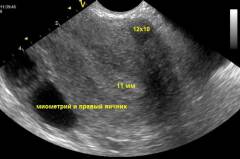

УЗИ яичников

Для визуализации яичников с помощью ультразвука используются два метода: трансабдоминальное и трансвагинальное УЗИ.

Характеристики методов:

- Трансабдоминальный доступ требует заполнения мочевого пузыря, что улучшает прохождение звуковых волн и точность диагностики. Рекомендуемая частота — 3,5–3,75 МГц.

- Трансвагинальное исследование не требует заполнения мочевого пузыря. Датчик располагается ближе к яичникам, что делает метод более надежным и информативным. Рекомендуемая частота — 5–10 МГц. Однако этот метод требует высокой квалификации врача, так как изображение может быть искажено.

Эхографические показатели могут варьироваться в зависимости от возраста пациентки и фазы менструального цикла. Врач должен учитывать эти изменения при обследовании.

Основные параметры при обследовании яичников

| Параметр | Нормальный показатель | Особые указания |

| Объем органа | 5,5 – 10 см³ | Рассчитывается по трем измеренным размерам, перемноженным и деленным пополам. |

| Размер фолликулов | 0,4 – 0,6 см | В начале цикла визуализируются несколько фолликулов с незначительными различиями в размерах. |

| Граафов (доминантный) фолликул | 1 – 2 см | Начинает расти после 10 дня цикла, скорость роста — 0,1–0,2 см в день, остальные фолликулы уменьшаются. |

| Средняя длина яичника | 3 — 4 см | Параметры могут изменяться в зависимости от фазы цикла или наличия кист. |

| Средняя ширина яичника | 2 – 2,5 см | |

| Средняя толщина яичника | 1 – 1,5 см | |

| Физиологическая киста яичника | Диаметр до 5 см | Может изменять размеры и исчезать со временем. |

Яичники располагаются позади и немного сбоку от мочевого пузыря и матки. При трудностях с визуализацией врач может выполнить маневр, смещая матку через влагалище. Также возможно исследование в положении стоя или на боку.